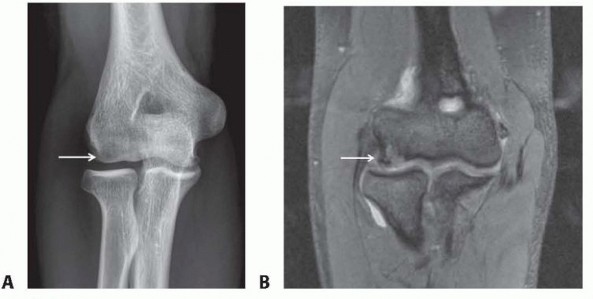

Open Reduction and Internal Fixation of Displaced Lateral Condyle Fractures of the Humerus Chapter 5 Open Red…